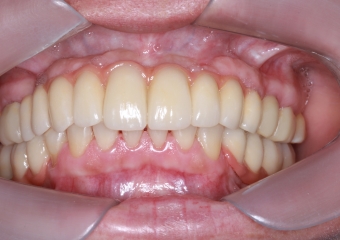

Imagem Final

Sorriso Final